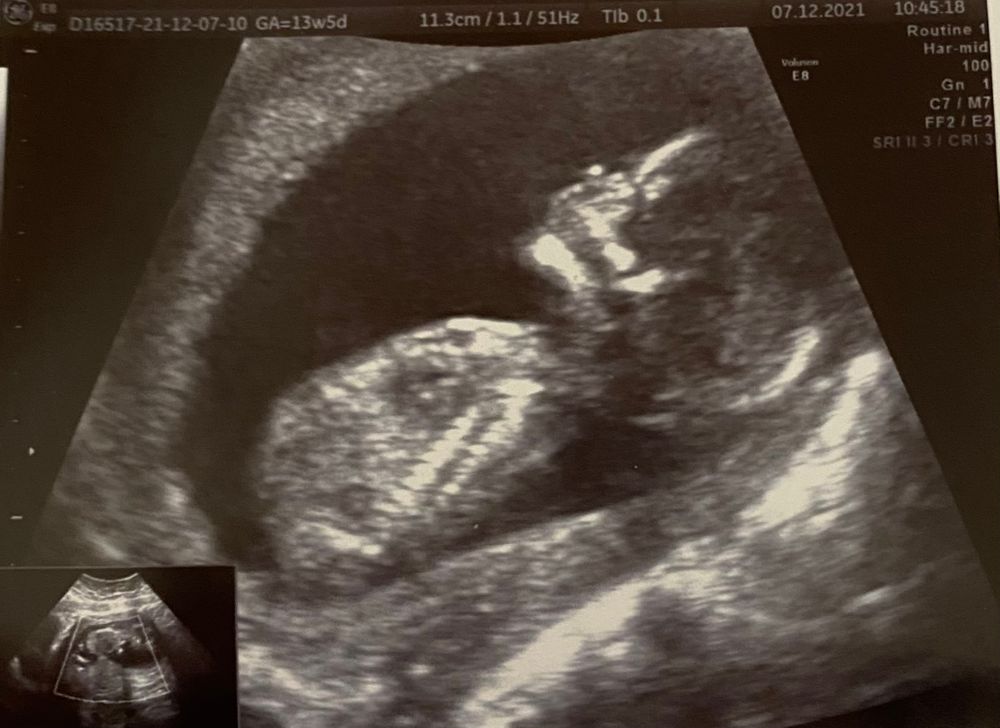

14 недель. Снимок УЗИ и мои ощущения. Кто рядышком? Делитесь ощущениями)

Какой замечательный снимок! Как все четко! У меня сейчас по УЗИ 14.2, а официально -13.2))) токсикоз прошел, ура. Полюбила капусту квашеную и тушёную и трясусь по роллам, впадаю в экстаз от селёдки под шубой. Животик уже такой, что сомнений мало вызывает. Тоже начала чувствовать, что кто-то копошится, сегодня было прямо как-то щекотно. Это точно оно, опыт уже есть, хотя по сроку рановато. Пол уже знаем: на УЗИ видно и нипт сдавали.

Dashushonok, у меня по УЗИ последний раз ставили 14+3 ,хотя на тот момент было 13+4 вроде 😅 А на счёт снимка да,сама аж довольна,в альбом хоть можно положить, а то остальные прям смазанные. Ну а тут прям человечище!😂 живот у меня уже неделю где-то «невтягиваемый» ,все что можно из одежды давит 🙄